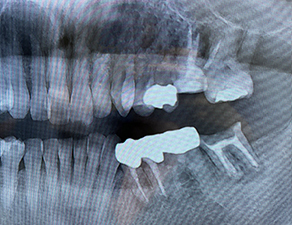

治療前の説明をしっかり行い、虫歯の治療、予防、歯科矯正、義歯の治療、ホワイトニングなど患者さまそれぞれのニーズに合わせた最新の治療の提供を心がけています。 お口の中の悩みがある方はぜひ一度小松歯科医院に足をお運びください。